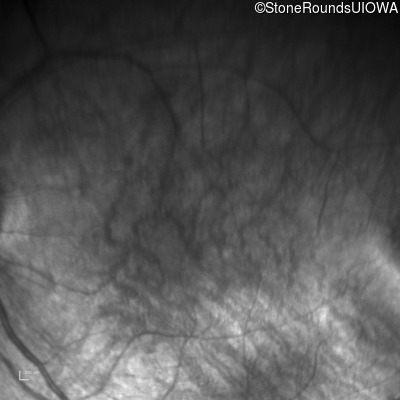

Infrared Fundus Photograph - Right - 10/300 sc

Exemplar